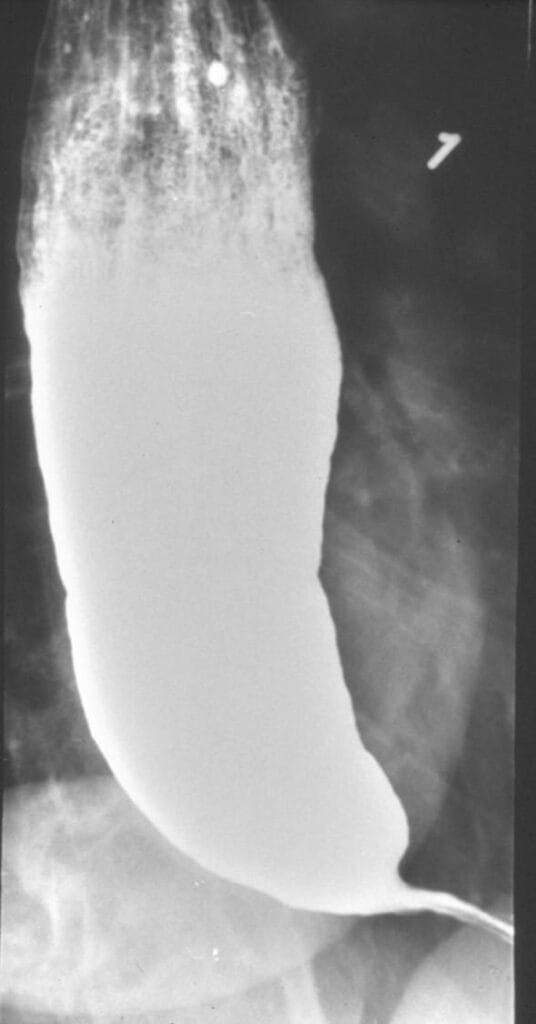

The pathophysiology of achalasia was eventually described in 1929 by Hurst and Rake.5 Using barium radiographs, they found that the distal esophagus was significantly dilated in patients with achalasia, evidenced by failure of barium passage across the LES. Normally, the swallowing reflex reduces LES tone and would allow barium to transit through the LES. This was not seen in those with achalasia. They proposed that achalasia is, in fact, not due to a mechanical obstruction but occurs because of a failure of LES relaxation. Later researchers used histopathological studies to advance understanding of this mechanism, finding that degeneration of ganglion cells in the Auerbach plexus, which are nestled in between the longitudinal and circular muscular layers of the LES and normally secrete nitric oxide to relax the LES, results in the inability of the LES to relax in achalasia.